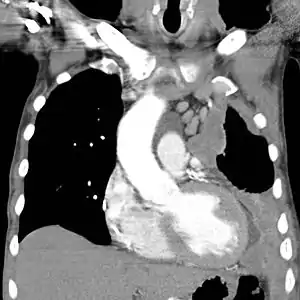

CT scan showing a left sided mesothelioma with an enlarged mediastinal lymph node